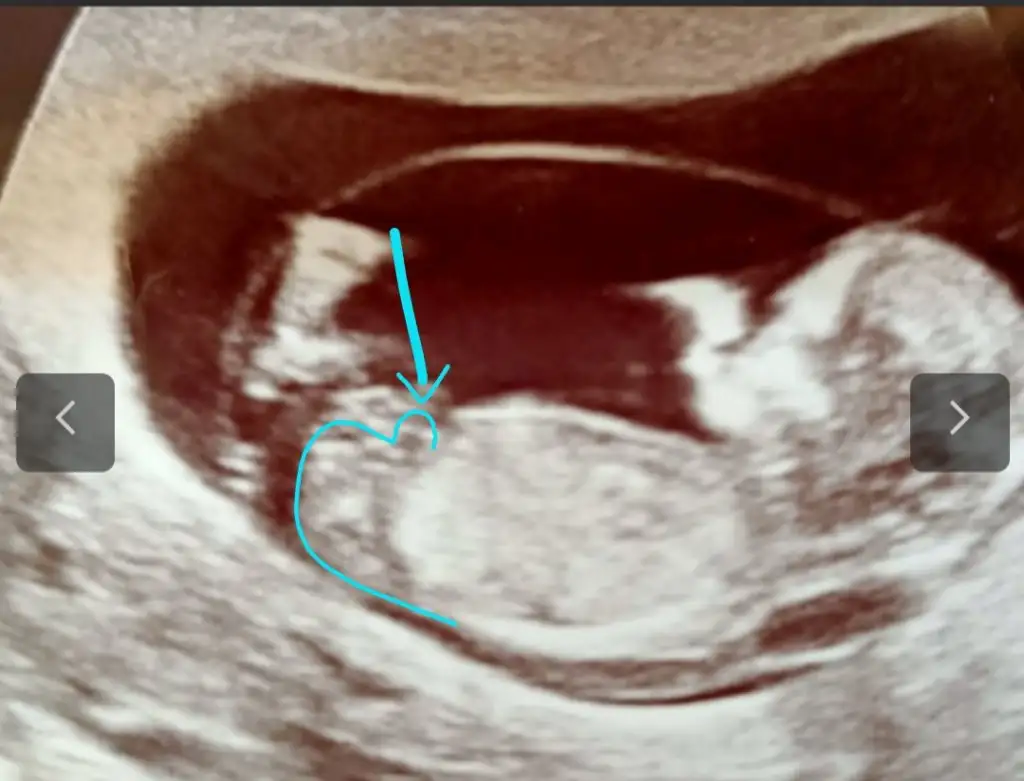

Belkide yanılmış olabilirim canım nubu çok karışık geldi bana yinede çizdim inşallah kızdır o nub değildir ilk bebekmiOvulasyon ile o kadarda takip ettim ama daha sizin diğer kız istiyenlerde takip etmiştim kısmet sağlık sıhhat versin teşekkürler

İkinci olucak kısmetse bir tane oğlum var kız olur diye çok umutlandık oğlumda kız olsun diyip duruyor hayırlısı Allah'tan diyelim ne diyelimBelkide yanılmış olabilirim canım nubu çok karışık geldi bana yinede çizdim inşallah kızdır o nub değildir ilk bebekmi

Erkek görünüyorBu bebiş erkek mi hanımlar

Erkek görünüyor